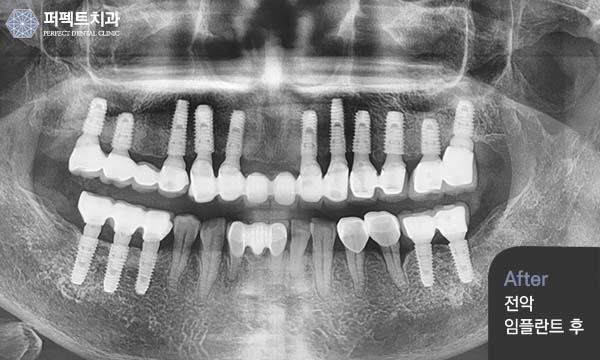

다양한 케이스들의 임플란트 수술과

퍼펙트치과는 다양한 케이스와

풍부한 임플란트 식립경험으로 임플란트를 찾는 환자분들에게

신뢰를 주고 만족하실 수 있는 치료를 하고 있습니다.